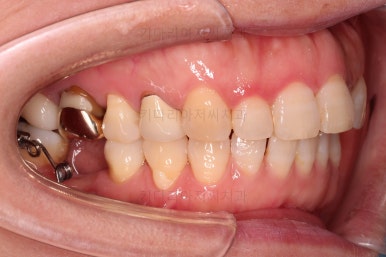

최종 사진을 보여드리겠습니다.

깔끔하게 마무리가 되었네요.

전후 비교입니다.

환자분도 치료에 만족하시어 미적으로 보기싫은 다른 금니들도 하나씩 교체하고 계신 중입니다.

이상 미니스크류를 이용하여 쓰러진 어금니를 연산동부분교정하고, 임플란트를 식립한 치료사례였습니다.